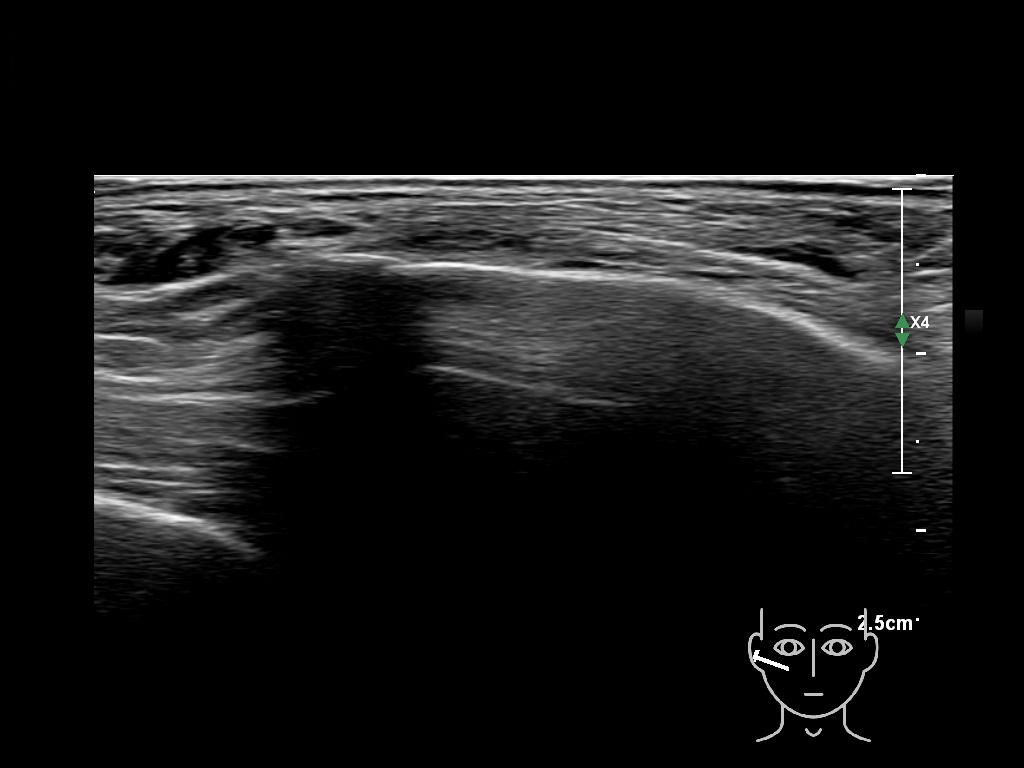

Filler behavior - Temple zygoma US

Study the first image to recognize the different layers. If you are sure about the layers, swipe to the second image to view the answer (if applicable).

Hover over an image to view the secondary image or click on the image title for more information.